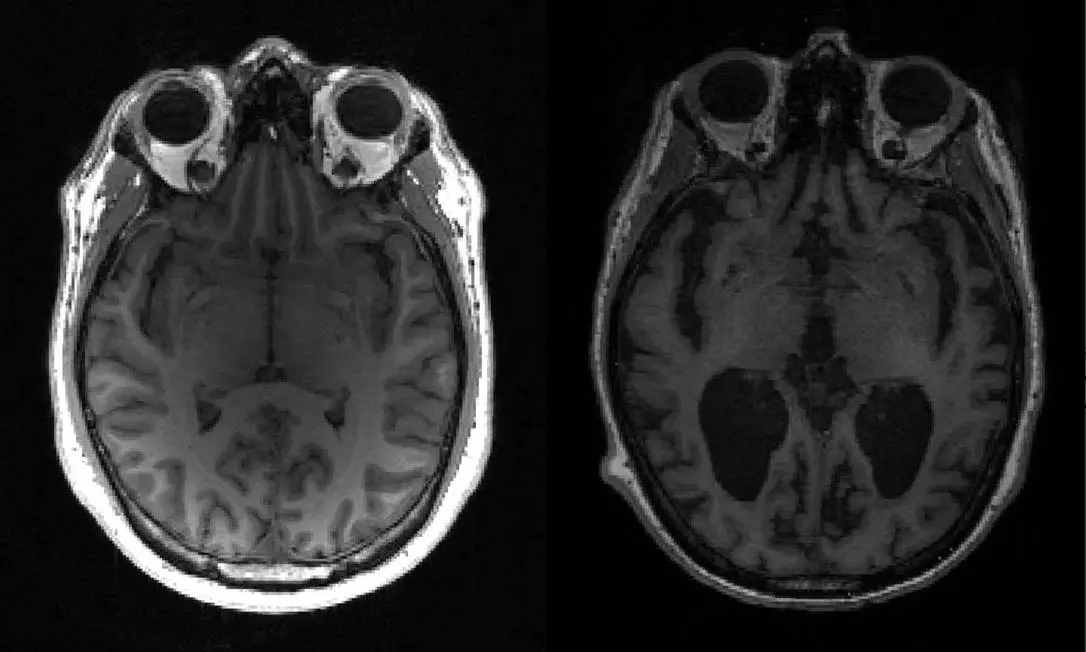

Legenda: À esquerda, um cérebro saudável. À direita, um cérebro com Alzheimer, apresentando grandes áreas escuras.

Foto: Timothy Rittman/AFP